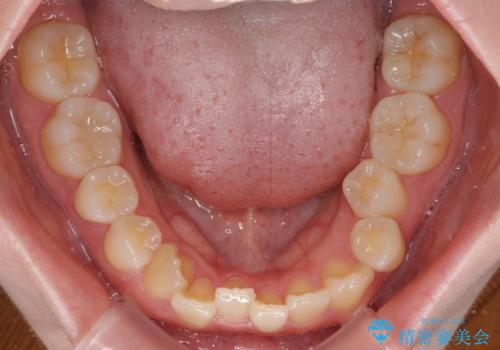

ディープバイトをインビザライン矯正で改善

- 前歯のデコボコと強い咬みしめを気にして来院された患者様です。

インビザラインを用いて、前歯の叢生を解消するとともに、ディープバイトを改善していくこととしました。

上顎に乳歯が左右1本ずつ残っていたため、若干咬み合わせに不具合が残りましたが、強い咬合力の原因であったディープバイトをしっかりと改善することができました。